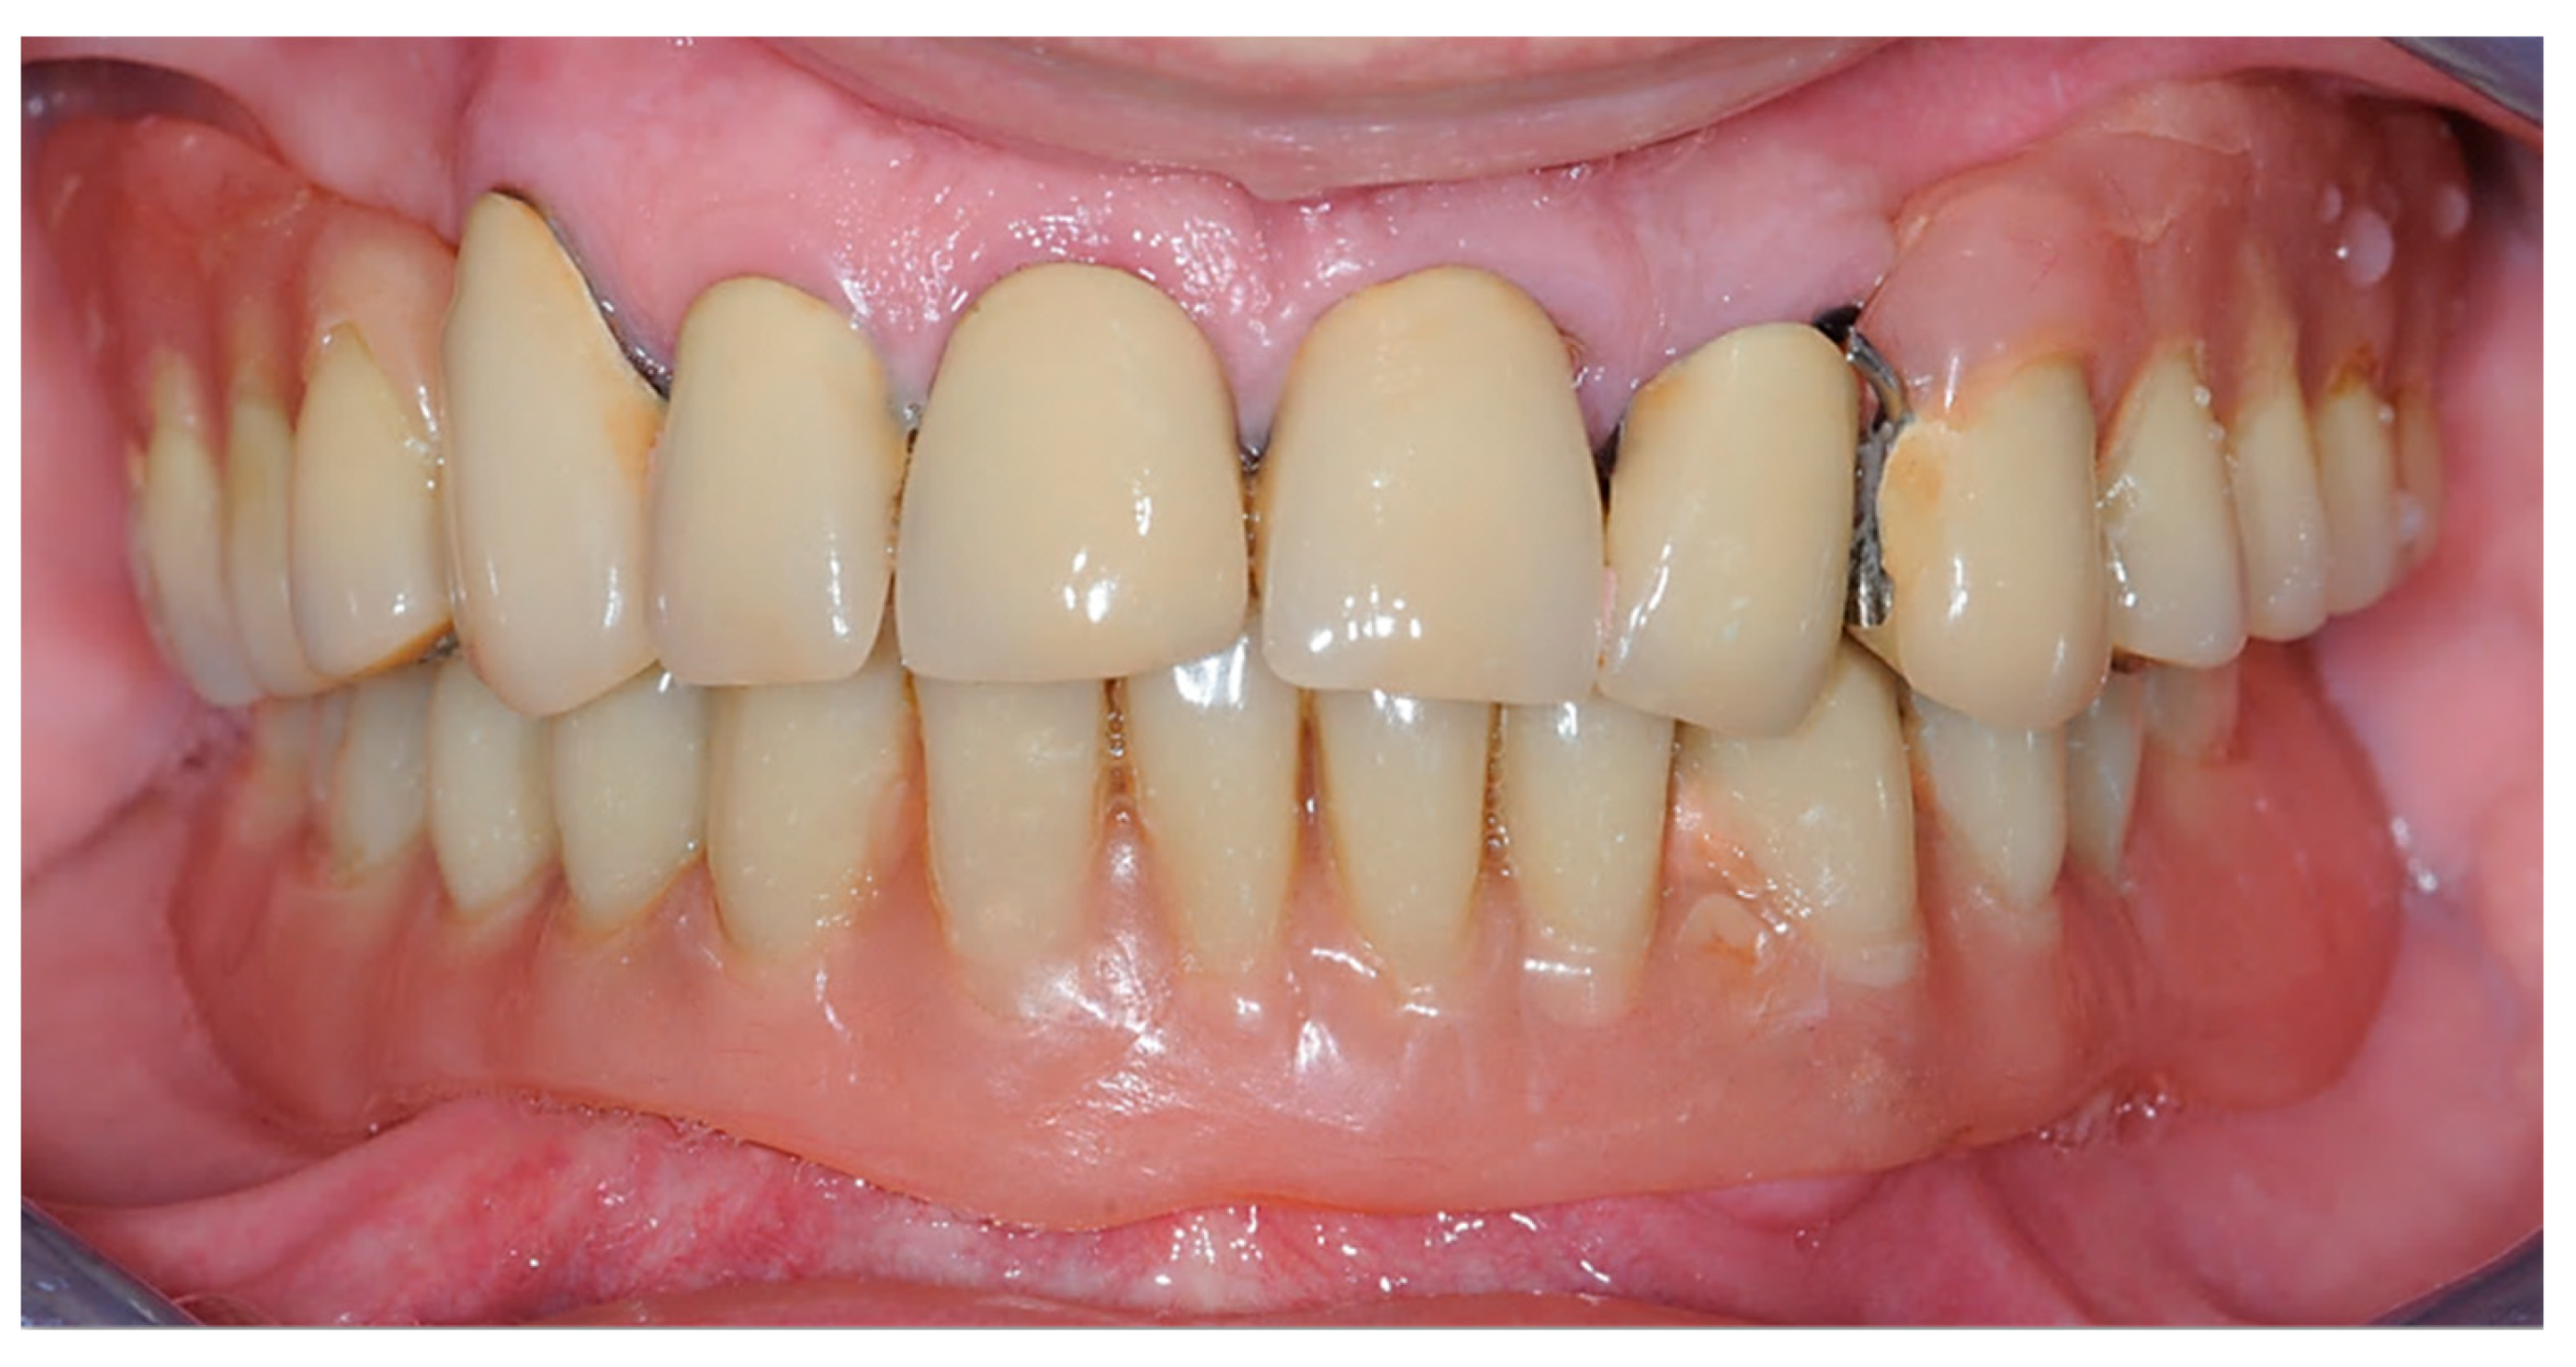

2.1. First Step: Complete Fixed Rehabilitation